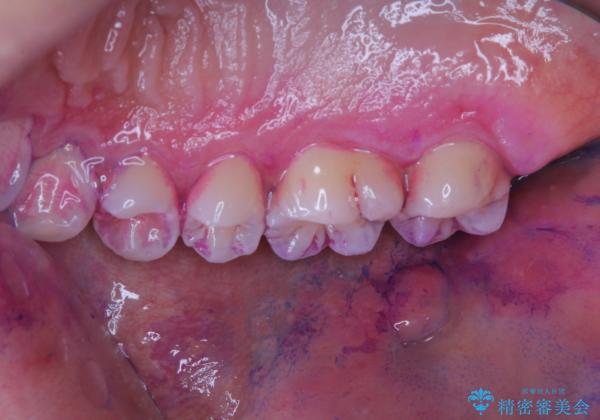

染め出しをして磨き残しのチェックと歯のクリーニング

染め出し液を使ってプラークを染め出すことにより、普段の歯みがきで磨き残している場所を目で確かめることができます。

日々の歯磨きを上達するには、まずどこが磨けていないか認識することが大切です。